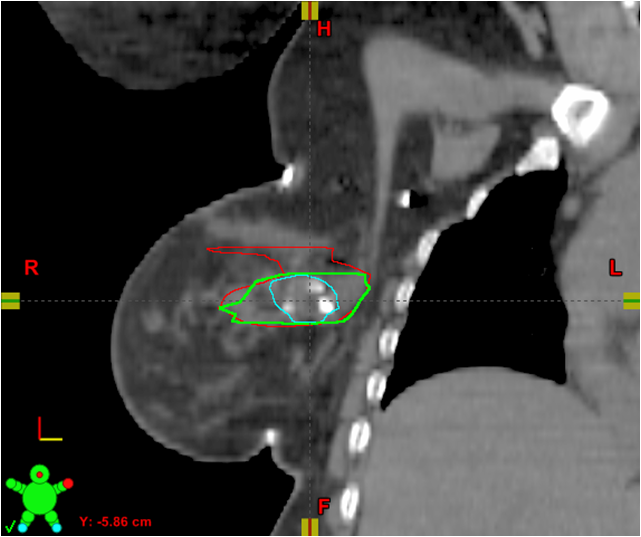

These CT images show placement of a 3-D fixed array implanted fiducial (3-D marker) at the time of oncoplastic tumor resection. The original LCTV (LCTVo) was retrospectively re-contoured by the radiation oncologist (LCTVro) and breast surgeon (LCTVbs). Thereafter, both re-contours were combined to create the collaborative LCTV (LCTVc), which required agreement of both the radiation oncologist and breast surgeon. Volume differences between the original LCTV (LCTVo) and the collaborative LCTVc were then evaluated, and demonstrated a mean and median reduction in LCTV.

Our initial study of the implant involved our first 10 patients who had the device placed during their lumpectomy surgery. All of the patients had received OPS as part of their procedure. In the first phase of the study, patients received radiotherapy with standard target delineation techniques and were contoured by myself or one of my partners. In this phase, there was no collaboration between the surgeon and radiation oncologists. The volumes devised in the first phase were those used for patient treatment. In the next phase, Kaufman and I retrospectively and separately re-contoured the lumpectomy cavity volume (LCTV) for each patient with the implant informing our contour volume. We then combined our LCTVs to create a collaborative LCTV that we mutually agreed upon. The collaborative LCTV was substantially smaller than the target volume based on standard targeting methods.